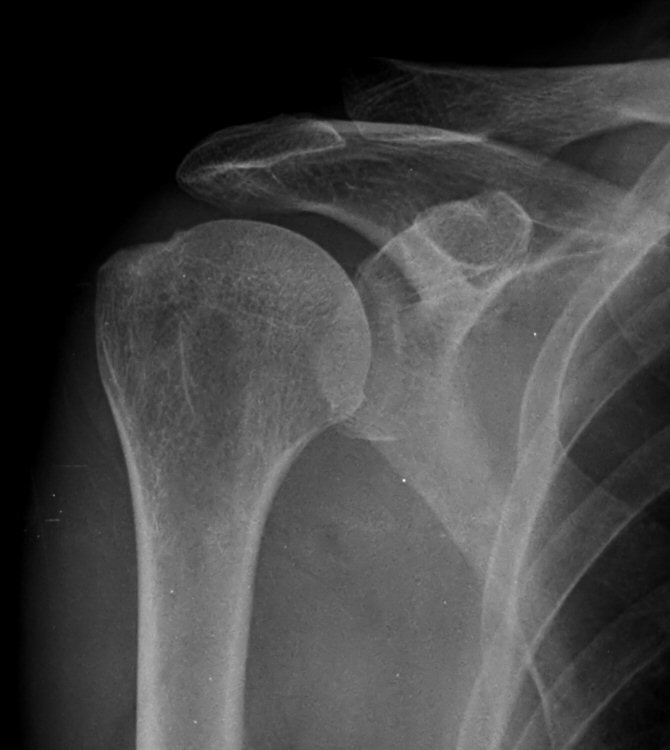

´ë°áÀý Ç¥¸é¿¡ ¹Ì¼¼ÇÑ ¿ïÅüºÒÅüÇÔÀÌ °üÂûµÊ(»çÁø 10)

¹æ»ç¼±»çÁø°ú ÃÊÀ½ÆÄ »çÁø 6) 9)¿¡¼­ º¸ÀÌ´Â ´ë°áÀýÀÇ ¿ïÅüºÒÅüÇÑ ¸ð½Àµµ ±Ø»ó°Ç ÆÄ¿­À» ½Ã»çÇØ ÁØ´Ù.